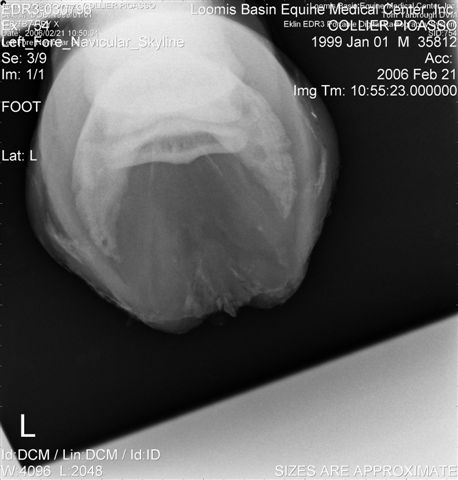

Let's label the radiographs from left to right with numbers. The abnormalities I see on the L using the photo's number as reference:

1) Odd lucency (darker) at the top/lateral margin of the coffin bone (seen in many images). It would interesting if this is also the site of the odd bruising.

2) Decrease lucency (darker) in the body of the navicular bone.

2) Remarkable cone shape areas of decrease lucency (darker) along the distal margin of the navicular bone.

3) Assymetrical flexor surface of the navicular bone.

4) There is the appearance of poor ap balance of the foot with the heels being low

4) Soles appear thin

4) Small osteophyte (bone spur) on the front margin of the pastern joint.

On the right the main problem is the appearance of the n. bone in the first image. It appears to have large irregular areas of increased lucency surrounding areas of decreased lucency. The darker areas (decreased lucency) may be artifacts or represent thinning of cortical bone.

Unless there is something I am missing in the images the extensor process appears to have healed well on the L. The significance of each of these lesions will depend on clinical findings Ann and confirmation that these are actual lesions and not artifacts created by positioning or the foot preparation for radiography. You should note I am not a radiologist and that viewing images in this manner is not as revealing as viewing the radiographs first hand.